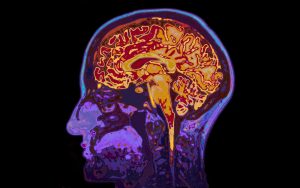

Mri,Image,Of,Head,Showing,Brain